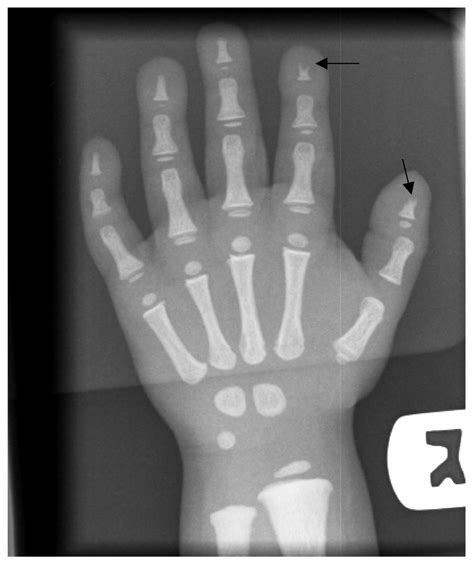

Modern medical science has largely moved away from the vague diagnostic umbrella of Toulouse Lautrec Syndrome, pointing instead toward a specific autosomal recessive condition known as pycnodysostosis. This rare disorder is characterized by dense, brittle bones and short stature, traits that align perfectly with the historical accounts of the artist’s life.

• Skeletal Fragility: Increased bone density often leads to a higher risk of fractures, which explains Henri’s childhood accidents.

• Shortened Limbs: Disproportionate growth between the trunk and the appendages is the most visible sign of the disorder.